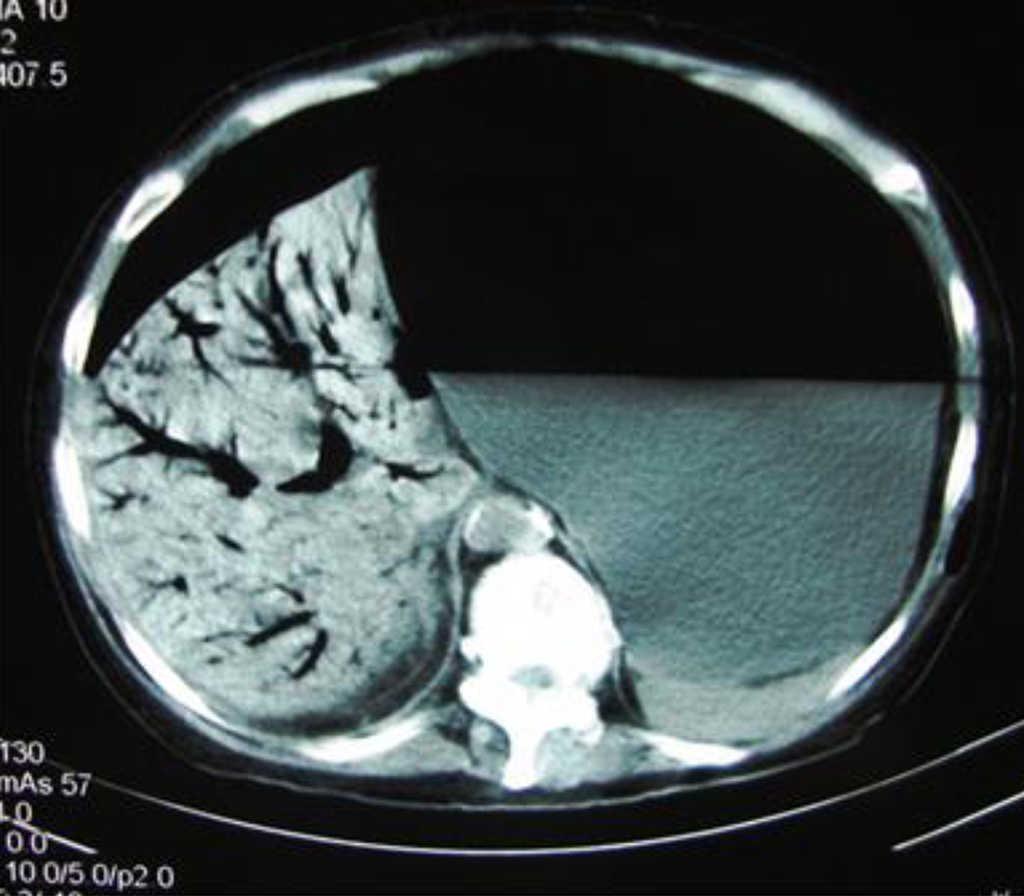

A 56-year-old woman was admitted to the emergency room with a one-day history of abdominal distension and epigastric pain. She started having symptoms after bowel preparation for colonoscopy. Abdominal CT scan showed an extremely distended stomach and small bowel (Figure 1), as well as gas in the hepatic-portal veins (Figure 2). Hepatic portal venous gas is a rare condition that occurs when intraluminal gas enters the portal venous circulation. Although there have been numerous reported causes, the majority are due to intestinal ischemia, with an estimated mortality rate of 75–80%. Mucosal barrier disruption of any kind can theoretically result in hepatic portal venous gas, but it appears to be more common in intestinal ischemia, inflammatory bowel disease, and peptic ulcer disease. Iatrogenic mucosal tears from endoscopy can also result in this situation. Diagnosis is usually made by plain abdominal radiography, sonography, color Doppler flow imaging, or computed tomography scan. An abdominal CT scan showed the classic sign of dilated vessels extending to within 2 cm of the liver capsule, in contrast to biliary gas, which ends up collecting centrally as a result of the centripetal movement of bile.

Figure 2.